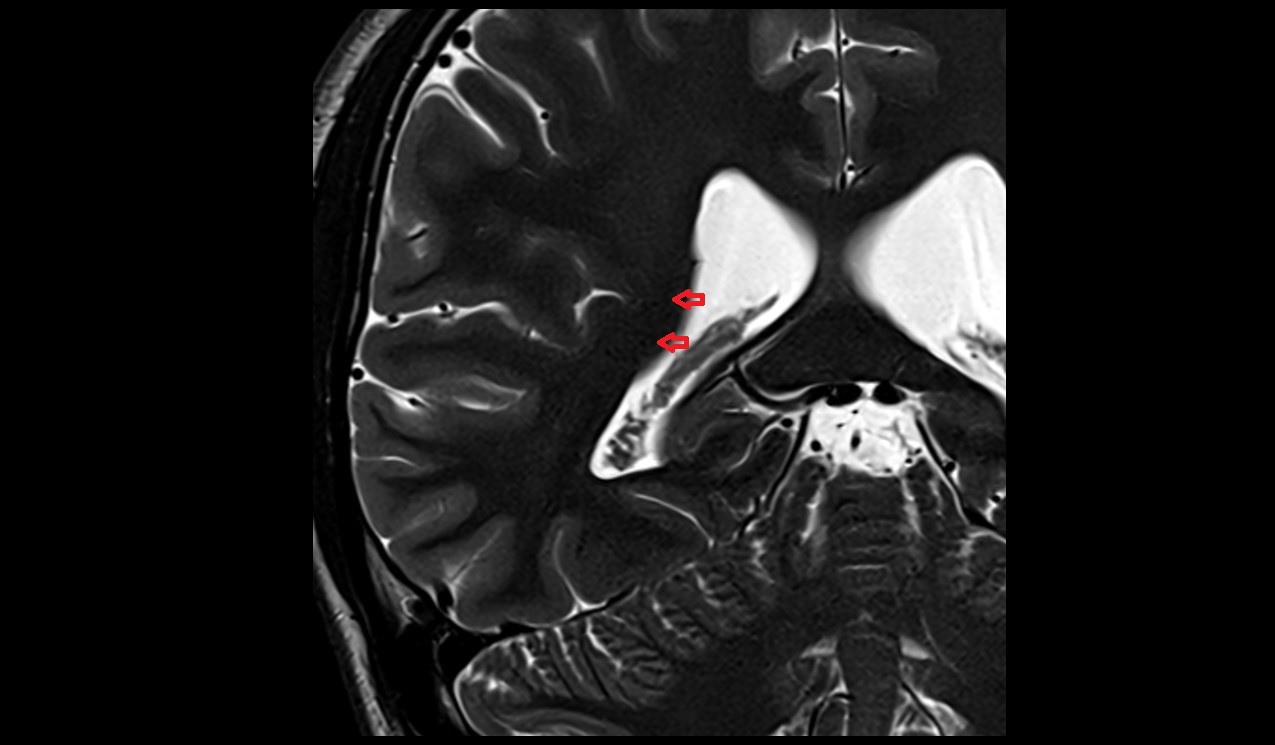

- Hippocampal head

- Head of hippocampus